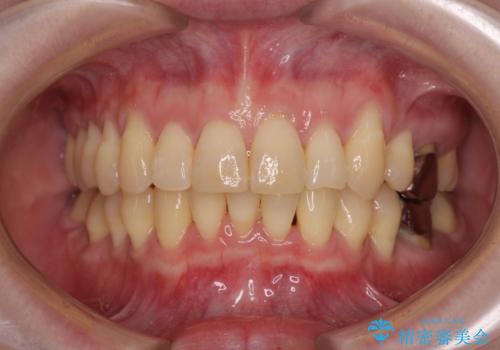

捻れて飛び出した前歯 インビザラインで整った前歯に

インビザラインによる上下歯列の側方拡大と後方移動、IPR(歯と歯の間を削る)にるスペースの獲得により歯列を整えることとしました。

歯と歯の間を削ることでうまくスペースコントロールでき、また、毎日22時間以上しっかりとマウスピースを装着していただいたので、スムーズに治療が進みました。

治療途中で転勤となり、遠方からの通院となったため、来院間隔空いてしまいましたが、2年間で終えることができました。